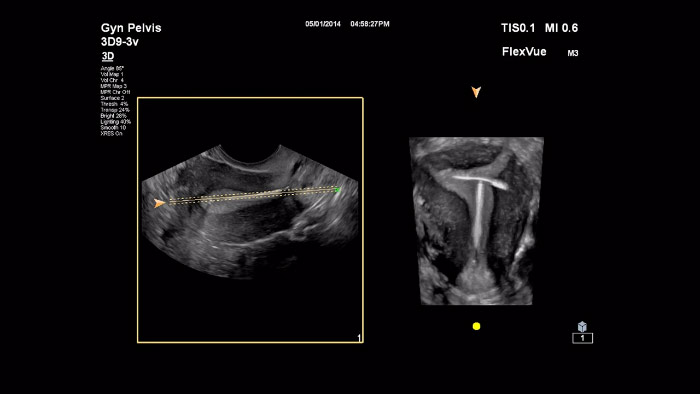

在该视频中,Michael Ruma 博士展示了 FlexVue 这一飞利浦高级三维评估工具。FlexVue 可以通过三维容积对技术难度较高的解剖视图进行可视化,这对妇产科病理诊断至关重要。